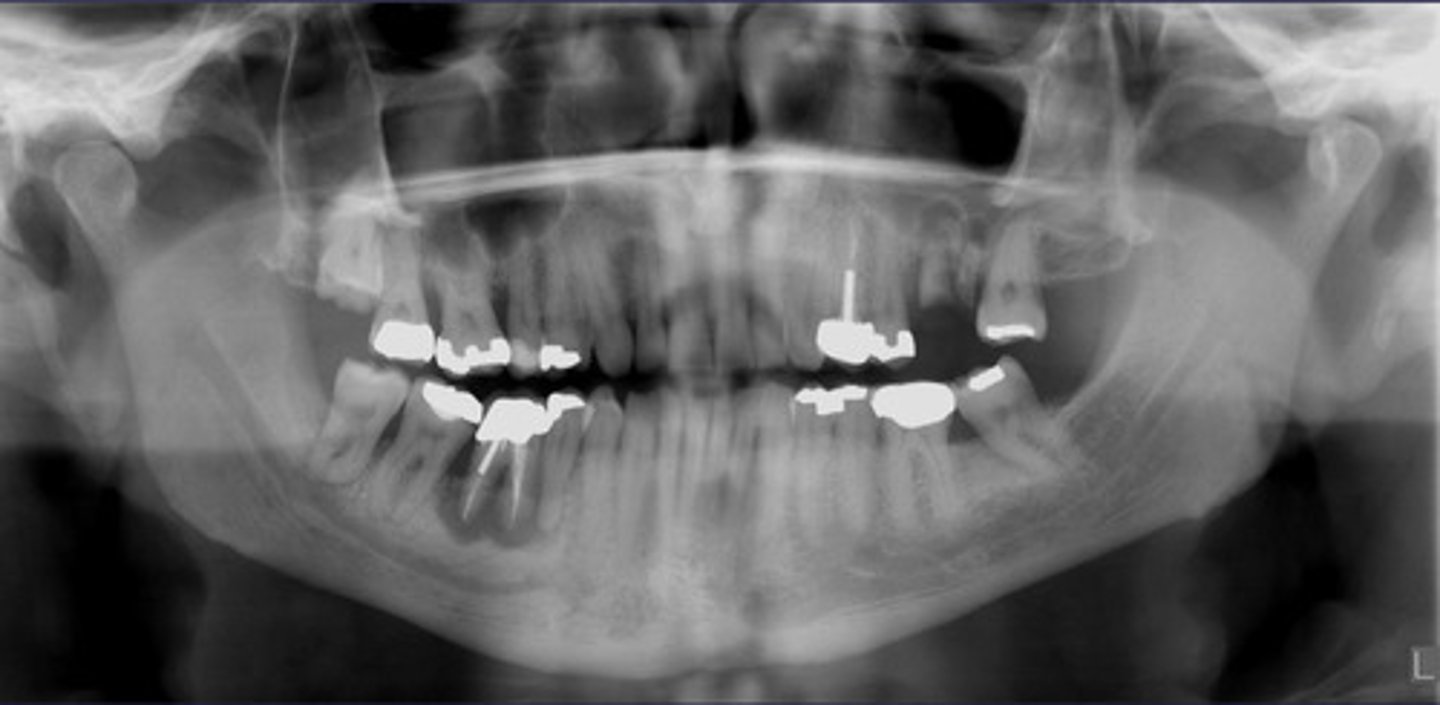

How would you describe the lesion?

- Ill defined, moth-eaten trabecular pattern in the entire mandible

- There is chronic periodontal bone loss associated with most mandibular teeth with furcation involvement and apical radiolucencies

- There is thinning of the inferior mandibular cortex.

- Can also be described as ill-defined areas of mixed radiolucent and radiopacities throughout the

mandible

What category would this lesion be part of?

Inflammation/Malignant

What would be a differential diagnosis for this lesion?

Chronic osteomyelitis

(DD: osteomyelitis, multiple myeloma)